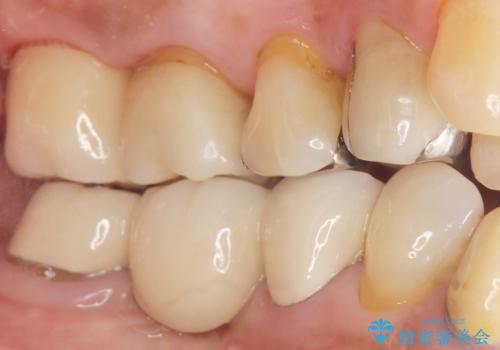

オールセラミッククラウンの審美的な仕上がりと自然な咬み心地に喜んで頂けました。

「ほかの金属も外してセラミックに変えていきたい」とおっしゃって下さいました。

クラウンの種類:オールセラミッククラウン スタンダード